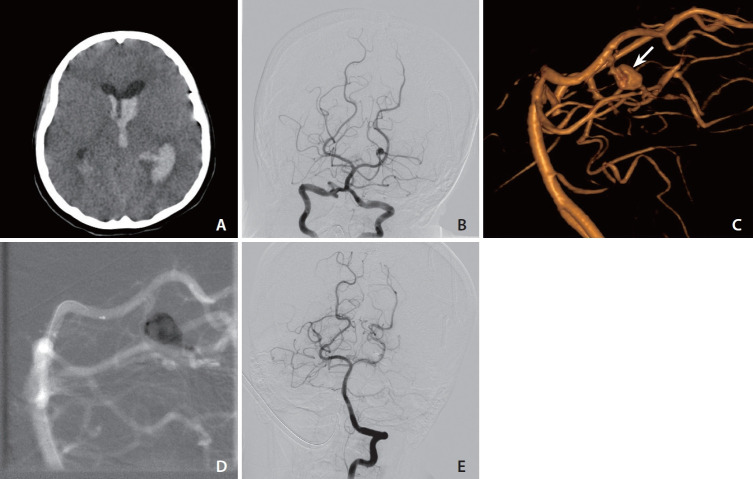

Purpose: Intracranial mycotic aneurysms (IMAs), rare and often life-threatening, result from arterial wall infections typically caused by bacteria such as Staphylococcus and Streptococcus. The standard treatment for ruptured aneurysms is not well-defined and often individualized. This study investigates the efficacy of endovascular glue embolization in managing ruptured IMAs, based on our center's experience.

Materials and methods: A retrospective analysis was conducted for ruptured IMAs treated with glue embolization between January 2016 and December 2023. The procedure involved aneurysm sac and parent vessel occlusion with glue delivery. Data included patient demographics, clinical presentations, and neuroimaging. Clinical outcomes were assessed using the modified Rankin scale (mRS) at 3 months, and angiographic follow-up was conducted at 6 months.

Results: The study included 28 patients, predominantly male (64.3%), with a mean age of 48 years. Headache was the primary symptom in 92.9% of cases, and positive blood/cerebro spinal fluid cultures were found in 82.14% of cases. All aneurysms were located in the distal circulation, primarily in the anterior circulation system. Glue embolization was successfully performed in all cases, achieving complete aneurysm sac and parent vessel obliteration. Follow-up at 3 months indicated mRS scores of 0 or 1 in 96.5% of cases. Six-month angiographic follow-up showed no aneurysm regrowth or new formations.

Conclusion: Endovascular glue embolization demonstrated high efficacy and safety in treating ruptured IMAs, with a 100% obliteration rate and favorable clinical outcomes in this single-center experience. Despite limitations such as its retrospective design and small sample size, the study supports glue embolization as a viable, less invasive alternative to traditional surgery. Further comparative studies are needed to confirm these findings and refine treatment approaches.